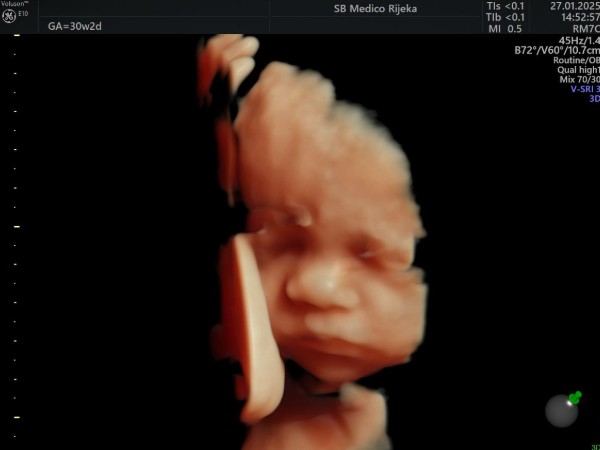

3D/4D ultrazvuk – trenutak koji ostaje zauvijek

Suvremeni 3D/4D ultrazvuk donosi novu dimenziju praćenja trudnoće. Omogućuje detaljniji prikaz razvoja djeteta prilikom svakog pregleda, a budućim roditeljima pruža priliku da na ekranu jasno vide lice svog djeteta, njegove pokrete i geste.

Iako je riječ o dijagnostičkoj metodi koja pomaže liječnicima u procjeni razvoja fetusa, taj pregled često ima i snažnu emocionalnu vrijednost, jer je to trenutak u kojem roditelji prvi put “upoznaju” svoju bebu.

U Medicu se 3D/4D ultrazvuk obavlja na najsuvremenijim uređajima visoke rezolucije koji omogućuju iznimnu jasnoću slike, a stručni tim ginekologa osigurava preciznu analizu i ugodno iskustvo pregleda.

Osim što doprinosi sigurnosti trudnoće, taj pregled mnogim roditeljima ostaje jedna od najljepših uspomena, jer je često to prvi osmijeh, zijevanje ili pokret njihove bebe koji imaju prilike vidjeti.